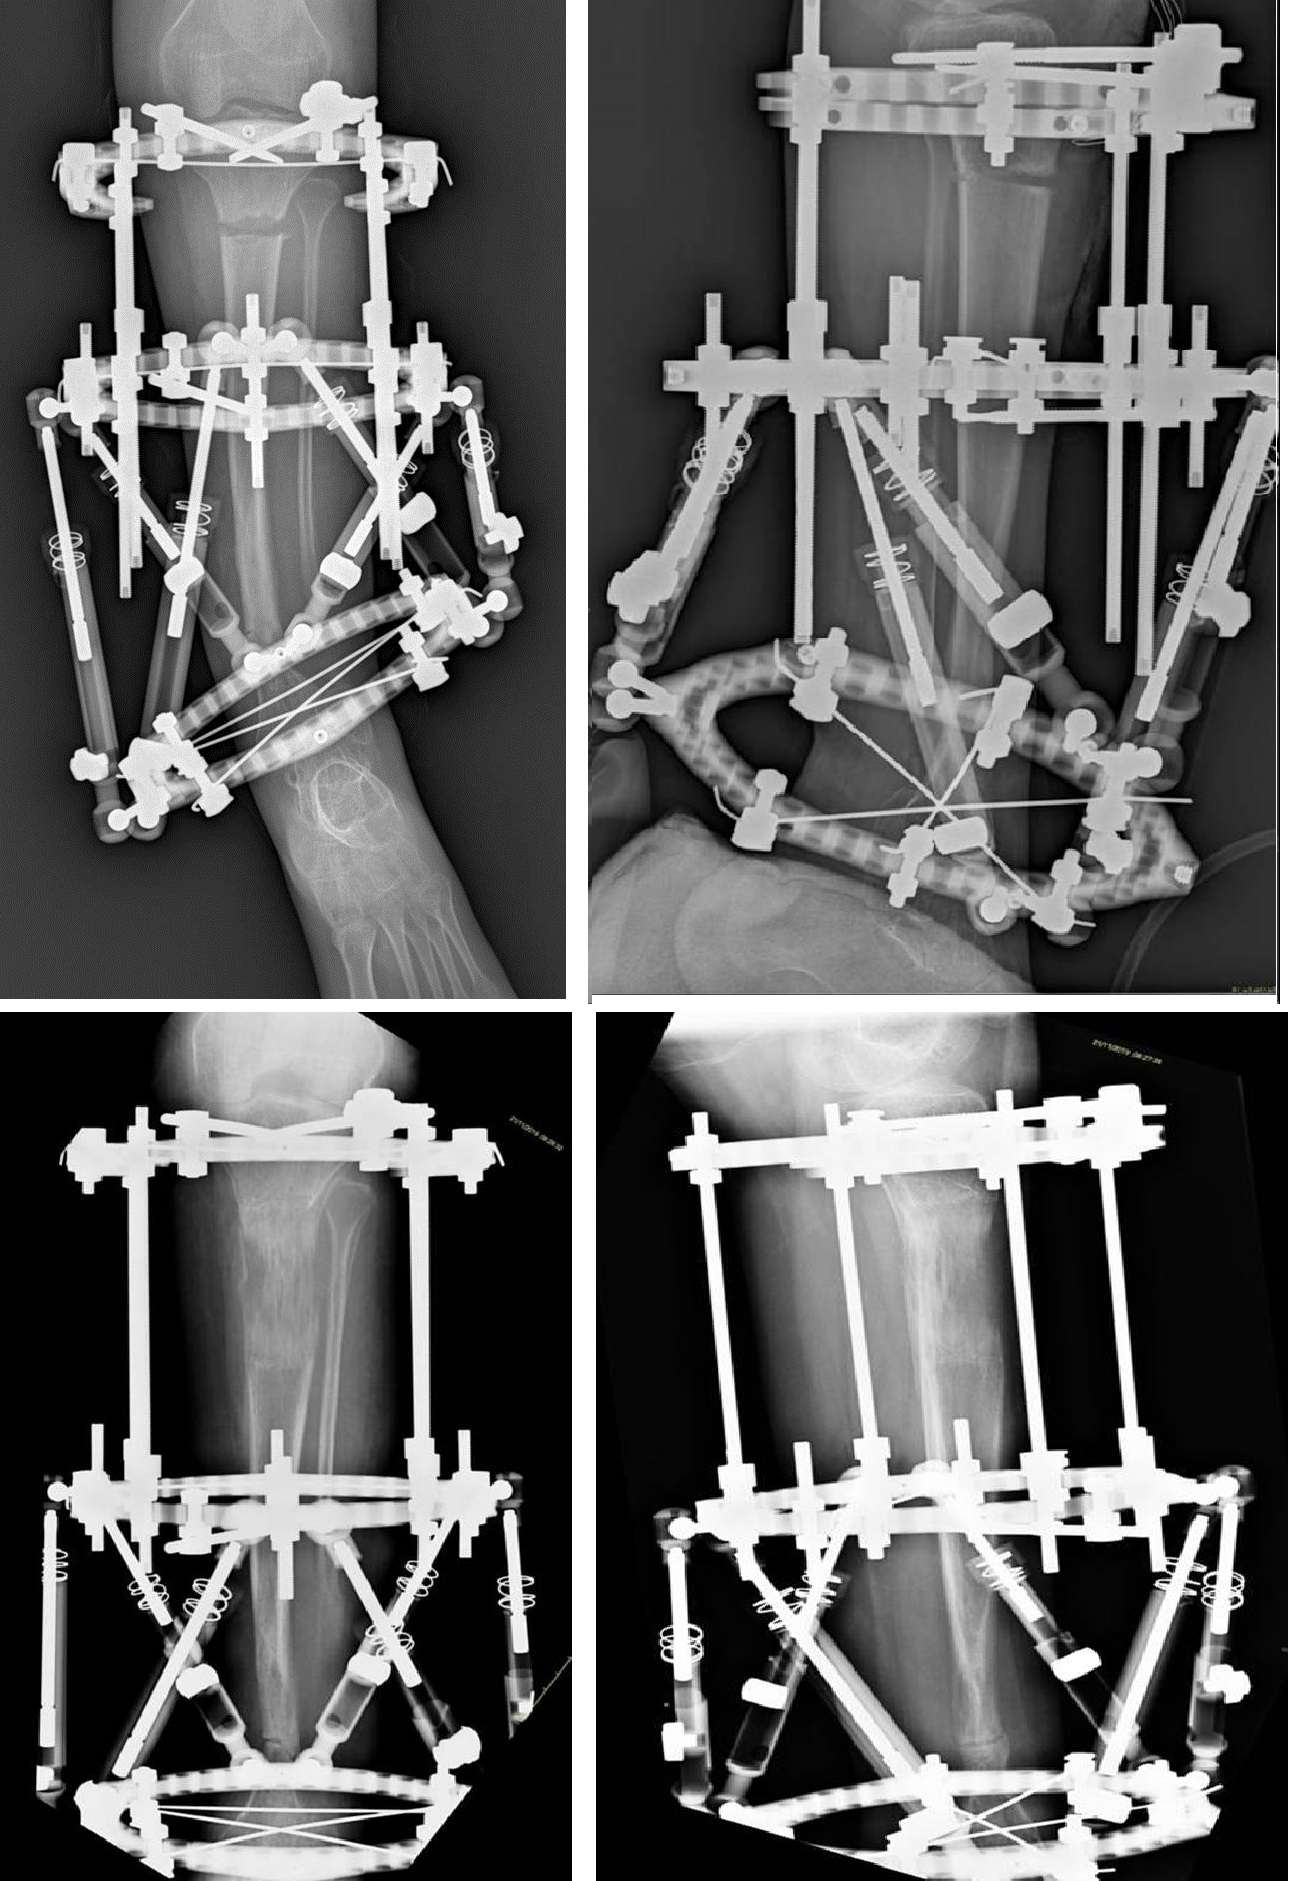

2) Secondo tipo di fissazione si ottiene mediante uso di fissatore esterno (Ilizarov o moderni esapodali), in genere utilizzato nei pazienti più grandi, come intervento definitivo per correggere le deformità residue e l'accorciamento dell'arto oppure per trattare la pseudoartrosi e contemporaneamente recuperare l'accorciamento associato o meno ad adiuvanti biologici.